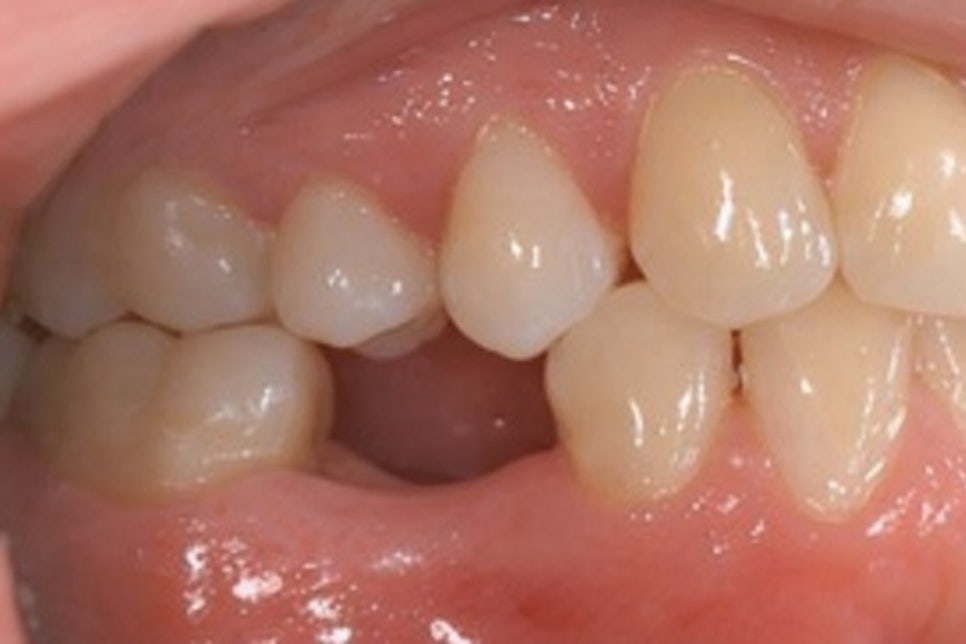

<인접치 이동 및 치열 변화>

치아는 서로 맞물리면서

균형을 이루고 있기 때문에

한 치아가 빠지면 주변 인접치들이

빈 공간으로 서서히 기울어지거나 이동하게 됩니다.

이러한 변화는 치열의 균형을 무너뜨리고

음식물이 더 쉽게 끼게 만들어

우식이나 치주질환의 위험을 높일 수 있습니다.

<반대편 대합치 정출>

위아래로 맞물리던 치아 중 하나가 사라지면

반대편 대합치는 더 이상 저작 시

접촉할 대상이 없어지면서 점차 내려오거나

올라오는 현상이 발생합니다.

이를 정출이라 하며 교합 관계가 흐트러져

저작 기능에 불편감을 일으킬 수 있습니다.